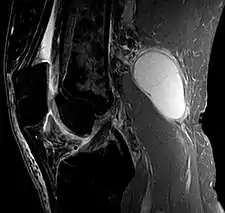

A Baker's cyst, also known as a popliteal cyst, is a type of fluid collection behind the knee.[5] Often there are no symptoms.[3] If symptoms do occur these may include swelling and pain behind the knee, or knee stiffness.[1] If the cyst breaks open, pain may significantly increase with swelling of the calf.[1] Rarely complications such as deep vein thrombosis, peripheral neuropathy, ischemia, or compartment syndrome may occur.[3][4]

Risk factors include other knee problems such as osteoarthritis, meniscal tears, or rheumatoid arthritis.[1][4][5] The underlying mechanism involves the flow of synovial fluid from the knee joint to the gastrocnemio-semimembranosus bursa, resulting in its expansion.[1] The diagnosis may be confirmed with ultrasound or magnetic resonance imaging (MRI).[4]

Diagnosis is by examination. A Baker's cyst is easier to see from behind with the patient standing with knees fully extended. It is most easily palpated (felt) with the knee partially flexed. Diagnosis is confirmed by ultrasonography, although if needed and there is no suspicion of a popliteal artery aneurysm then aspiration of synovial fluid from the cyst may be undertaken with care. An MRI image can reveal presence of a Baker's cyst.